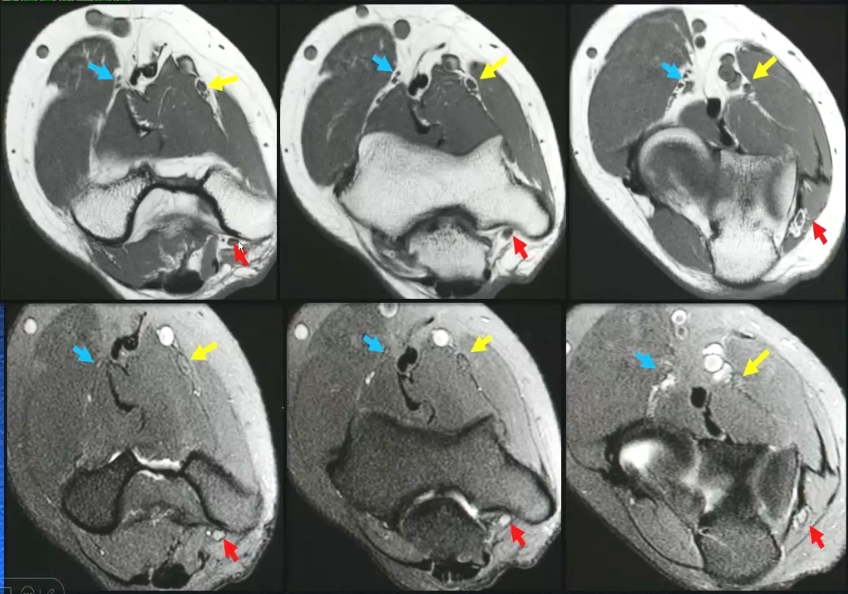

·尺神经:肘后三角—肱骨内上髁与尺骨鹰嘴间—尺神经沟

·正中神经:肱二头肌内侧间隙走行,穿旋前圆肌二头间于前臂正中

·桡神经:外上稞前下方,于肱桡肌与桡侧脘长伸肌间隙之间

·MRI:轴位观察为主,结合矢状位

T2WI稍高信号,电缆样结构